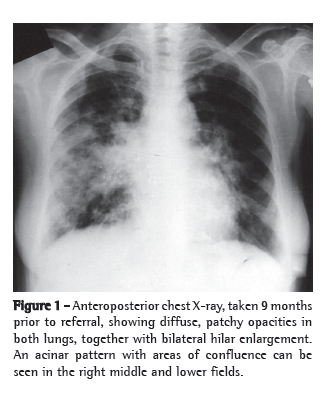

On reviewing a chest X-ray taken 9 months prior to referral, when antituberculosis therapy had been initiated, we observed diffuse, patchy opacities in both lungs, together with bilateral hilar adenopathy (Figure 1). An acinar pattern with areas of confluence was apparent in the right middle and lower fields. A CT scan of the chest, also obtained 9 months prior to referral, showed a well-defined cavitary lesion, not visible on the chest X-ray, in the anterior segment of the right upper lobe (Figure 2). In addition, we observed ground-glass opacities, accompanied by perihilar areas of consolidation and bronchovascular bundles with a beaded appearance. Bilateral hilar lymphadenopathy and asymmetric mediastinal lymphadenopathy, without caseation or rim enhancement, were also present. The cavitation seen on the CT scan probably prompted the initiation of the antituberculosis therapy. The laboratory evaluation at that time showed hemoglobin of 13.3 g/dL, with a total leukocyte count of 6,700 cells/mm3 and a normal differential leukocyte count. Although routine urine testing revealed traces of glucose, blood glucose values were within the normal range, since the patient was under treatment with oral hypoglycemic agents. The results of liver and kidney function tests, as well as the lipid profile and electrocardiographic findings, were also within normal limits. Sputum smear microscopy and culture for Mycobacterium tuberculosis and other aerobic organisms continued to yield negative results. Tuberculin testing with a 5-TU dose of PPD resulted in no induration.